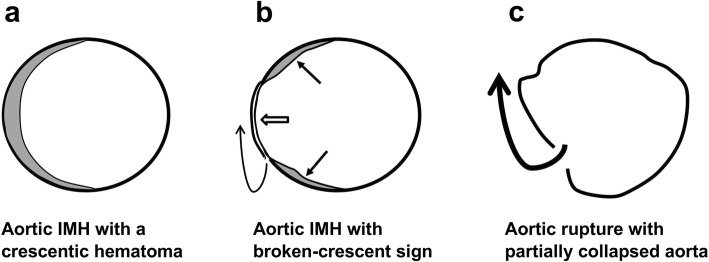

The hyper-attenuating crescent sign is seen in unenhanced CT as a localized curvilinear hyper-attenuating zone within the thrombus of abdominal aortic aneurysms and is an early sign of acute or impending rupture. It is caused by intrathrombotic hemorrhage and dissection of blood into the peripheral thrombus or aortic wall with the weakening of the support structure of the aneurysm incurring vulnerability to rupture [19, 20]. On the other hand, broken-crescent sign in IMH seems to exhibit different pathophysiological changes of the aortic wall. We postulate that acute aortic IMH may complicate with a subtle adventitial tear followed by partial outward seepage of an intramural blood clot, leading to a broken-crescent configuration on CT (Fig. 5). The CT features in patient 2 and surgical findings in patients 6 and 7 supported this postulation. Because the residual inner aortic wall remained intact, there was no contrast medium extravasation. Due to local wall thinning, focal outward bulging of the aortic lumen may have compressed on and sealing up the underlying adventitial tear temporarily; thus, the IMH spillage could be transiently alleviated, resulting in a short duration of clinical mitigation. More importantly, with such a weakened residual inner aortic wall at the site of the broken crescent, IMH patients might subject to a high risk of subsequent aortic rupture, as seen in the follow-up CT of patient 1. Notably, in our patients with positive broken-crescent sign ascribed to outward seepage of an IMH, the maximum IHM thickness (range 4–8 mm, mean 5.4 mm) was far thinner than the threshold (11 mm) used for predicting IMH complications [9, 10].

Fig. 5.

Sketch shows the postulation of the development of broken-crescent sign in CT. a Acute aortic IMH with typical hyper-attenuating crescentic hematoma along the aorta on axial CT. b Partial aortic adventitial tear with outward seepage of the hematoma (curve arrow), leading to a broken-crescent configuration (arrows). Focal out-bulging (open arrow) of the residual inner aortic wall results in temporary sealing of the underlying adventitial defect. c Rupture of the aorta through the weakened residual inner aortic wall (curve arrow) with partially collapsed aorta